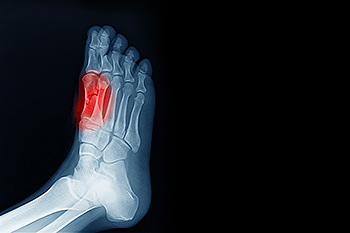

When Repetitive Stress Leads to Tiny Foot Fractures

Stress fractures are small cracks in a bone that form when repeated pressure outweighs the body’s ability to recover. These injuries often appear in people who increase activity too quickly, spend long hours on hard surfaces, or wear footwear that does not provide enough support. Early signs include a pinpoint ache that becomes sharper during walking or running, and eases with rest. Swelling or mild bruising may develop, and the discomfort usually returns the moment activity resumes. Although the fracture is small, leaving it untreated can lead to a complete break or long-lasting pain. Reducing impact, resting the foot, and adjusting footwear are important first steps toward healing. If you notice persistent pain in one spot on the foot or discomfort that worsens with activity, it is suggested that you schedule an appointment with a podiatrist for a proper evaluation and appropriate treatment.

How Are They Caused?

Stress fractures are the result of repetitive force being placed on the bone. Since the lower leg and feet often carry most of the body’s weight, stress fractures are likely to occur in these areas. If you rush into a new exercise, you are more likely to develop a stress fracture since you are starting too much, too soon. Pain resulting from stress fractures may go unnoticed at first, however it may start to worsen over time.

Stress fractures do not always heal properly, so it is important that you seek help from a podiatrist if you suspect you may have one. Ignoring your stress fracture may cause it to worsen, and you may develop chronic pain as well as additional fractures.